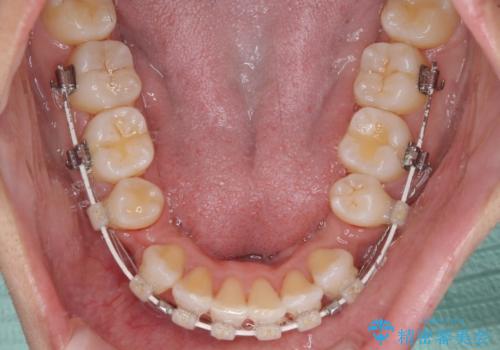

- 審美装置

- 2年3ヶ月

- 10-30回